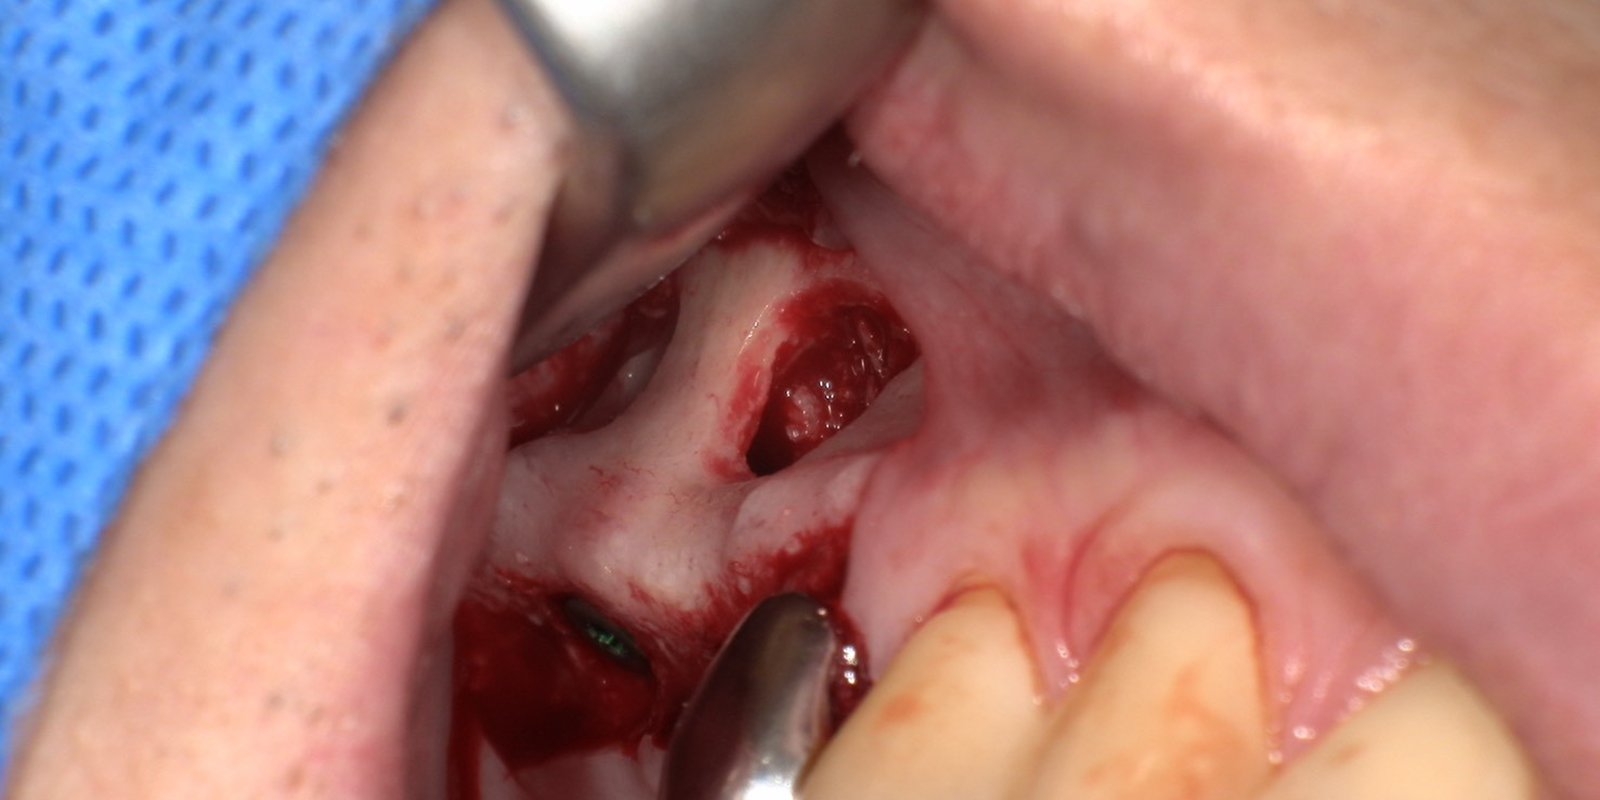

痛みが出ないように、麻酔をした後、歯肉頬粘膜を剥離翻転し、上顎洞側壁の骨を一部開けます。

骨窓を開けると、上顎洞粘膜にアクセスできるようになるため、上顎洞粘膜を穿孔しないように剥離します。インプラント体が埋入できる高さまで上顎洞粘膜を剥離します。

実際のオペの様子です。骨の窓開けがされており、上顎洞粘膜が挙上されている事が分かります。